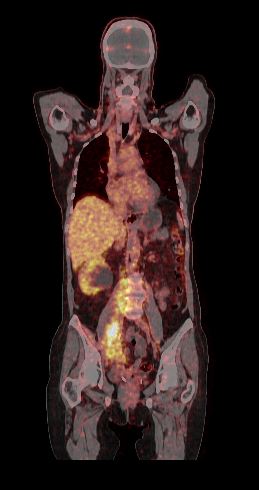

Narodowy Instytut Onkologii w Gliwicach rozpoczyna kolejne innowacyjne badanie immuno-PET

Gliwicki oddział Narodowego Instytutu Onkologii uruchomił pionierskie badanie kliniczne INTROSPECTION, w którym po raz pierwszy w Polsce wykorzystano nowy, wyprodukowany w Instytucie radioznacznik 89Zr-DFO-Pembrolizumab do obrazowania immuno-PET. Celem tego projektu jest sprawdzenie, jak radioterapia paliatywna, w tym radioterapia z przestrzennym zróżnicowaniem dawki, podawana samodzielnie lub w połączeniu z immunoterapią, modyfikuje odpowiedź układu odpornościowego u chorych, […]